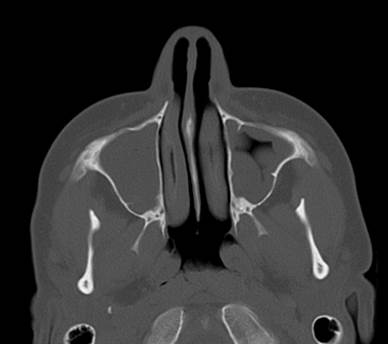

Полипозный этмоидит

Полипозный этмоидит 110 фото